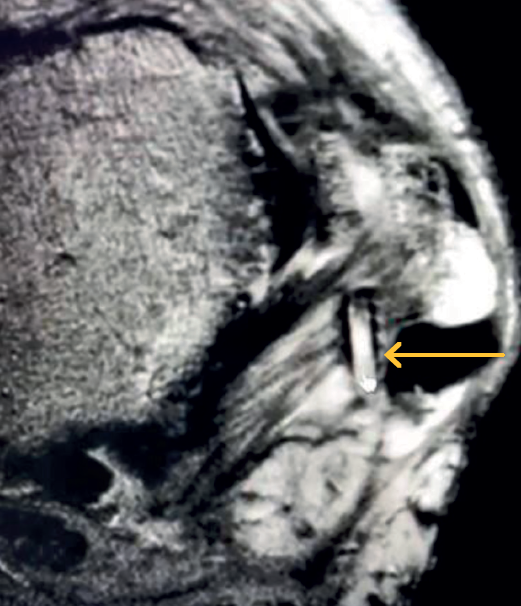

Hubo 3 pacientes (1%) con intolerancia a la sutura, que requirieron cirugía abierta (Figura 3). Tuvimos 2 casos (0,5%) de fracturas maleolares no desplazadas, una del maléolo medial y otra del maléolo peroneo, ocurridas durante la colocación del arpón en la reparación ligamentosa (Figura 4). Ninguno de estos pacientes requirió intervención adicional y fueron tratados con inmovilización durante 4 semanas, continuando con el protocolo de rehabilitación posterior. En otro caso (0,26%), se observó la migración del arpón hacia la parte posterior del peroné (Figura 5), diagnosticada a los 3 meses tras la cirugía; se decidió conducta expectante dada la ausencia de síntomas.

Batista et al.(16) han documentado 2 casos de lesión por el implante usado durante la reparación ligamentosa lateral. En nuestro estudio, tuvimos un caso de migración del arpón (0,26%) hacia la región retromaleolar lateral. Además, reportamos la recidiva como complicación en algunas patologías tratadas de manera artroscópica, como la inestabilidad lateral crónica de tobillo y el síndrome de fricción posterior de las partes blandas. Consideramos que los malos resultados en los casos de reparación del complejo ligamentoso lateral pudieron deberse a la mala selección de los pacientes y con un tejido remanente insuficiente.